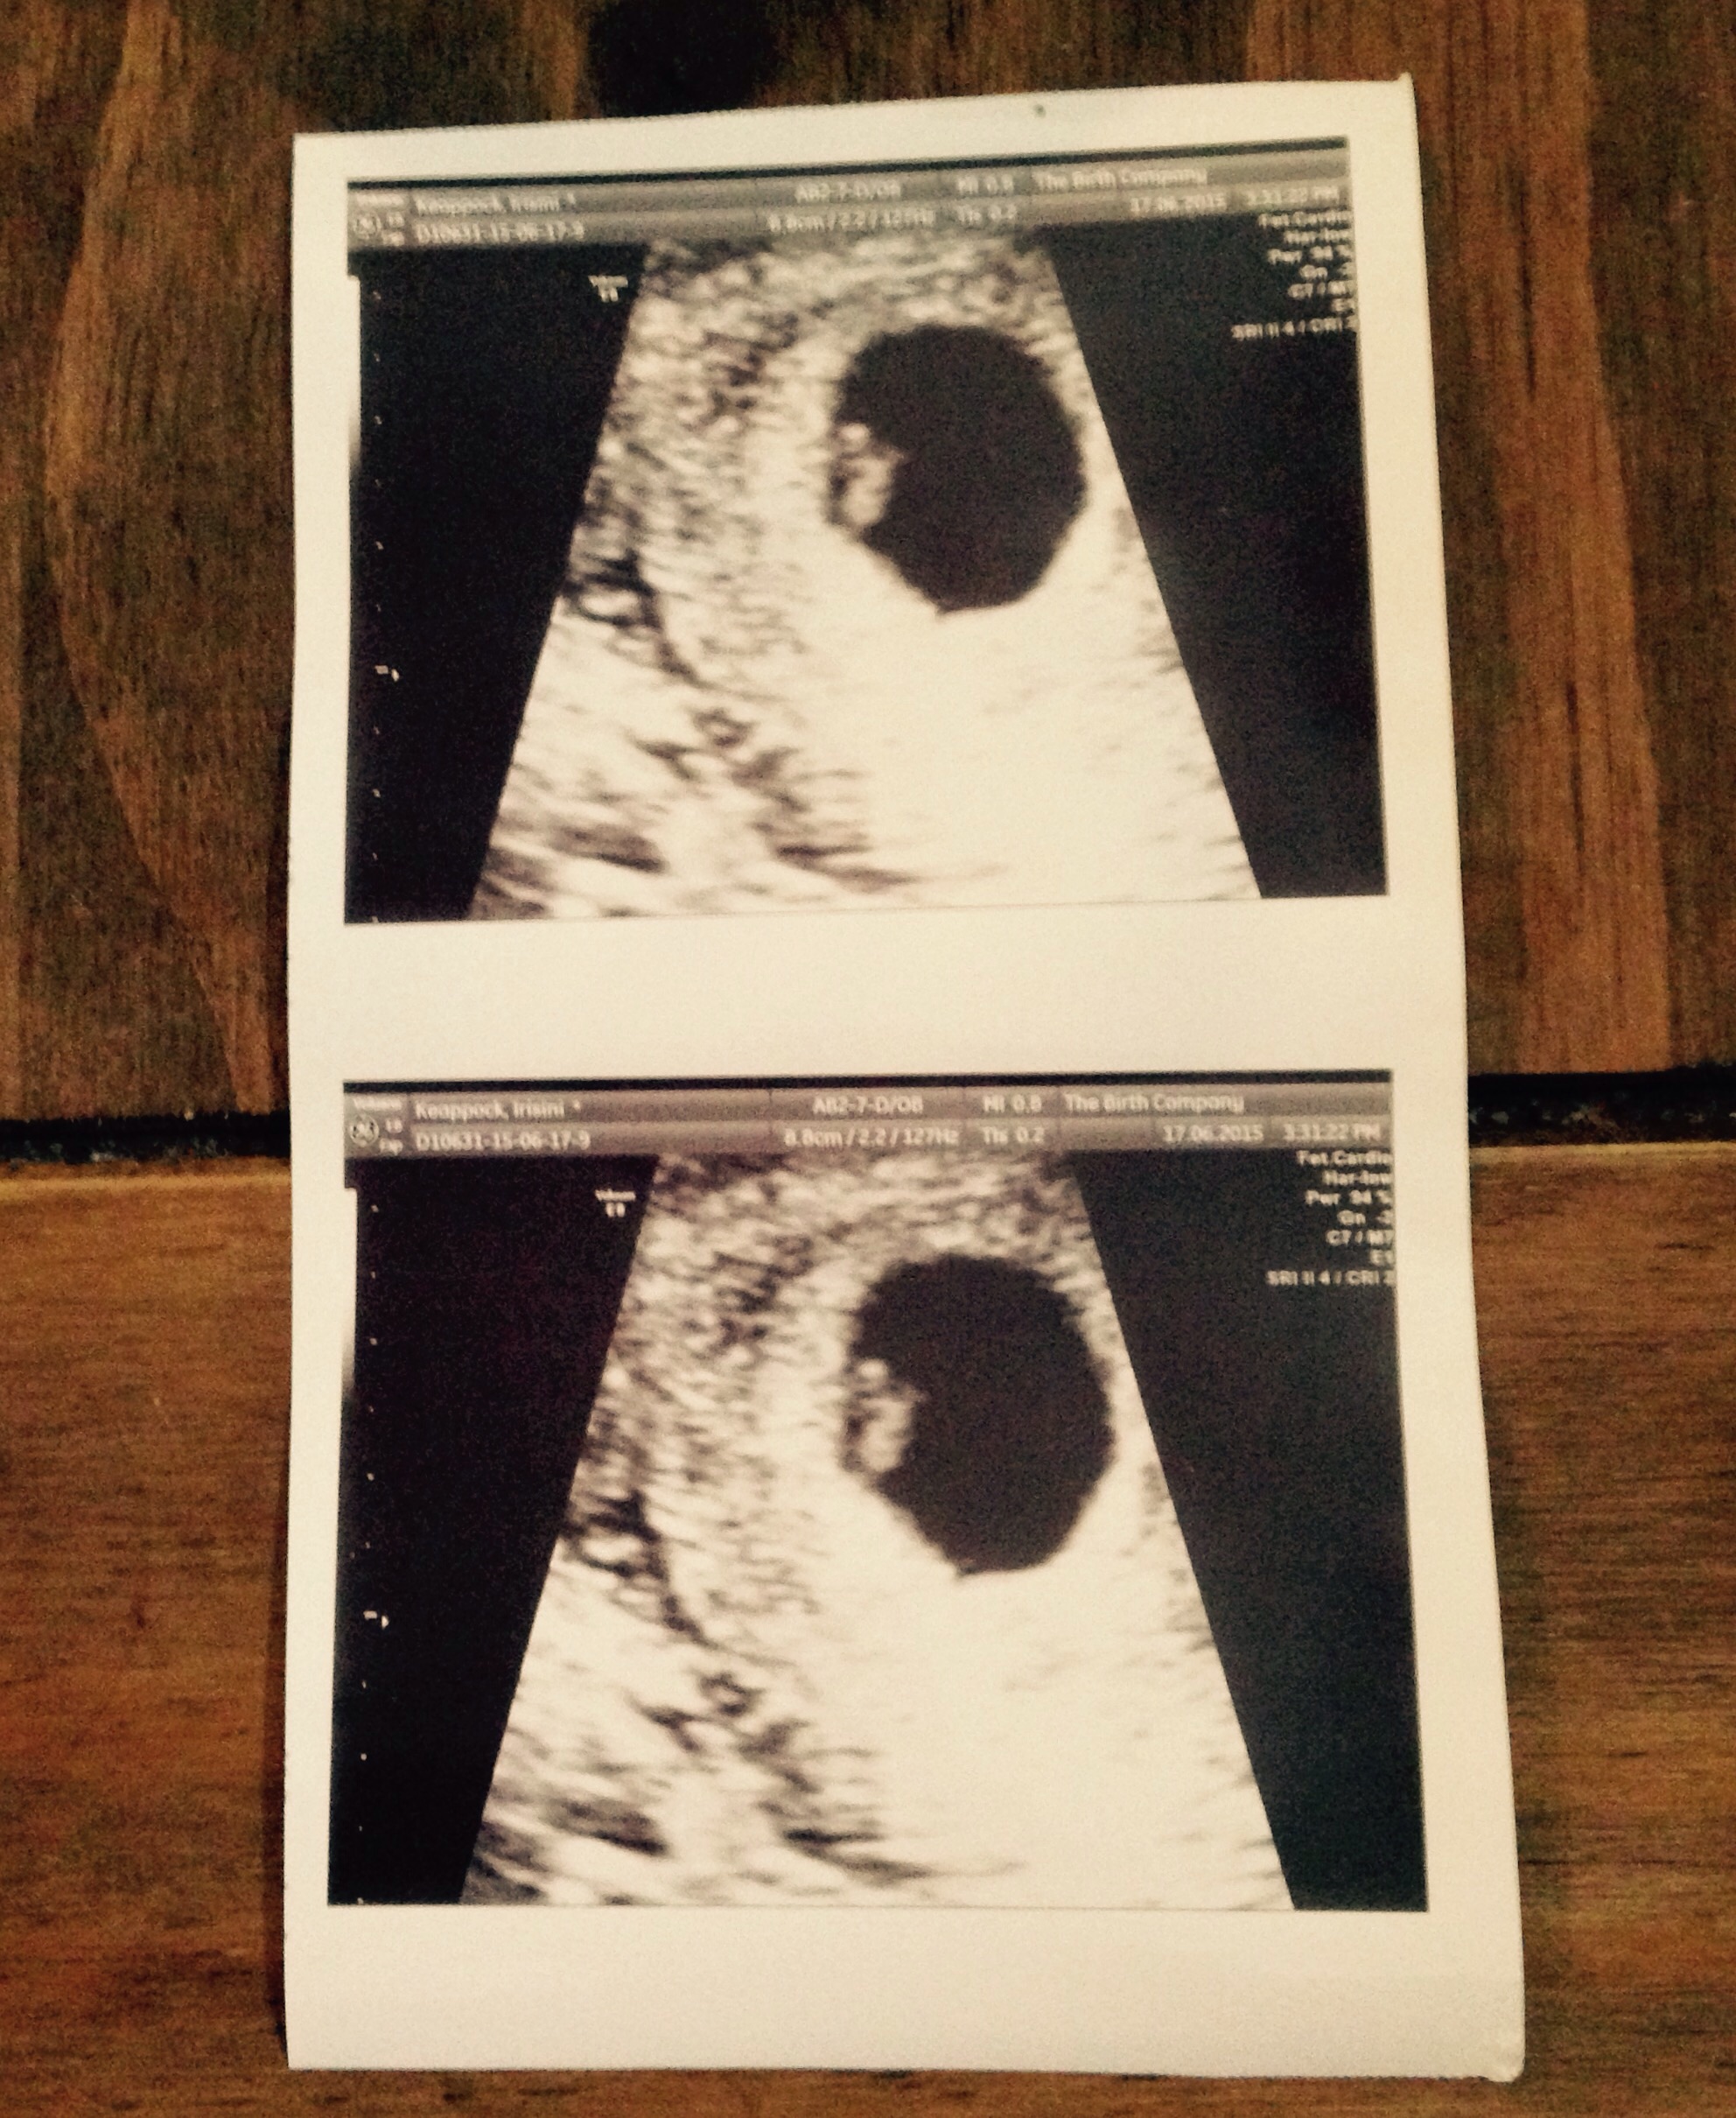

• Thanks @rs07151996! Had an u/s and got to hear and see the heartbeat! It blew my mind to say the least. You're right, the pains are normal per doctor and she couldn't find any abnormal reasons for the spotting. Dated 6w 5d based on the size of my little pumpkin which is surprising because I thought I was 3 days earlier! I'm going to sit and enjoy the ride for now